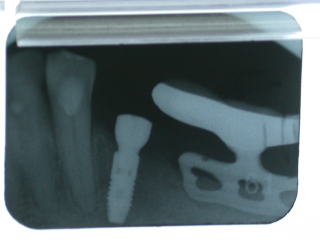

歯肉を開窓しヒーリングアバットメントを装着し、1週間程、歯肉治癒を待ちます。

歯肉が綺麗に治りました。